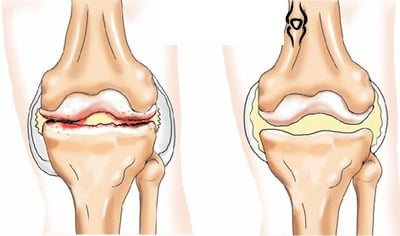

Происходит сужение суставной щели, хрящевая ткань повреждается в значительной степени. На снимке, полученном в ходе рентгенографии, можно заметить разрастания кости. Острыми болями сопровождается любое движение, в котором принимает участие коленный сустав. В состоянии покоя неприятные ощущения проходят, но затем появляются снова. К болям добавляется характерный хруст при совершении сгибательно-разгибательных движений.

Постепенно выполнение функции сустава становится невозможным. Колено перестает сгибаться и разгибаться. Внешне врач может определить деформацию костей.

Артроз коленного сустава 3 степени

Местами хрящевая ткань истончается окончательно, образуются обнаженные участки кости. На рентгенограмме хорошо заметно большое количество остеофитов — отложений солей в полости сустава. Кроме того, там могут быть обнаружены свободные тела.

Внешние изменения становятся все более заметными. Справиться с болью, прекратив движения, теперь не удается. Она сохраняется и при физических нагрузках на сустав, и в состоянии покоя.